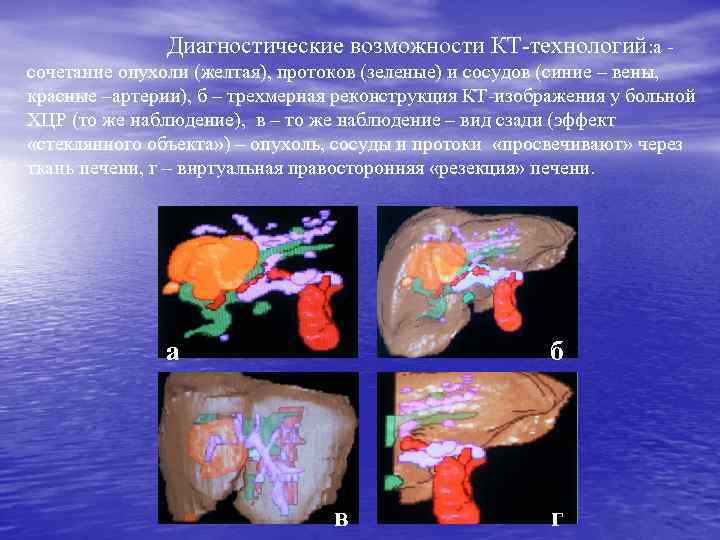

Диагностические возможности КТ-технологий: а сочетание опухоли (желтая), протоков (зеленые) и сосудов (синие – вены, красные –артерии), б – трехмерная реконструкция КТ-изображения у больной ХЦР (то же наблюдение), в – то же наблюдение – вид сзади (эффект «стеклянного объекта» ) – опухоль, сосуды и протоки «просвечивают» через ткань печени, г – виртуальная правосторонняя «резекция» печени. б а в г